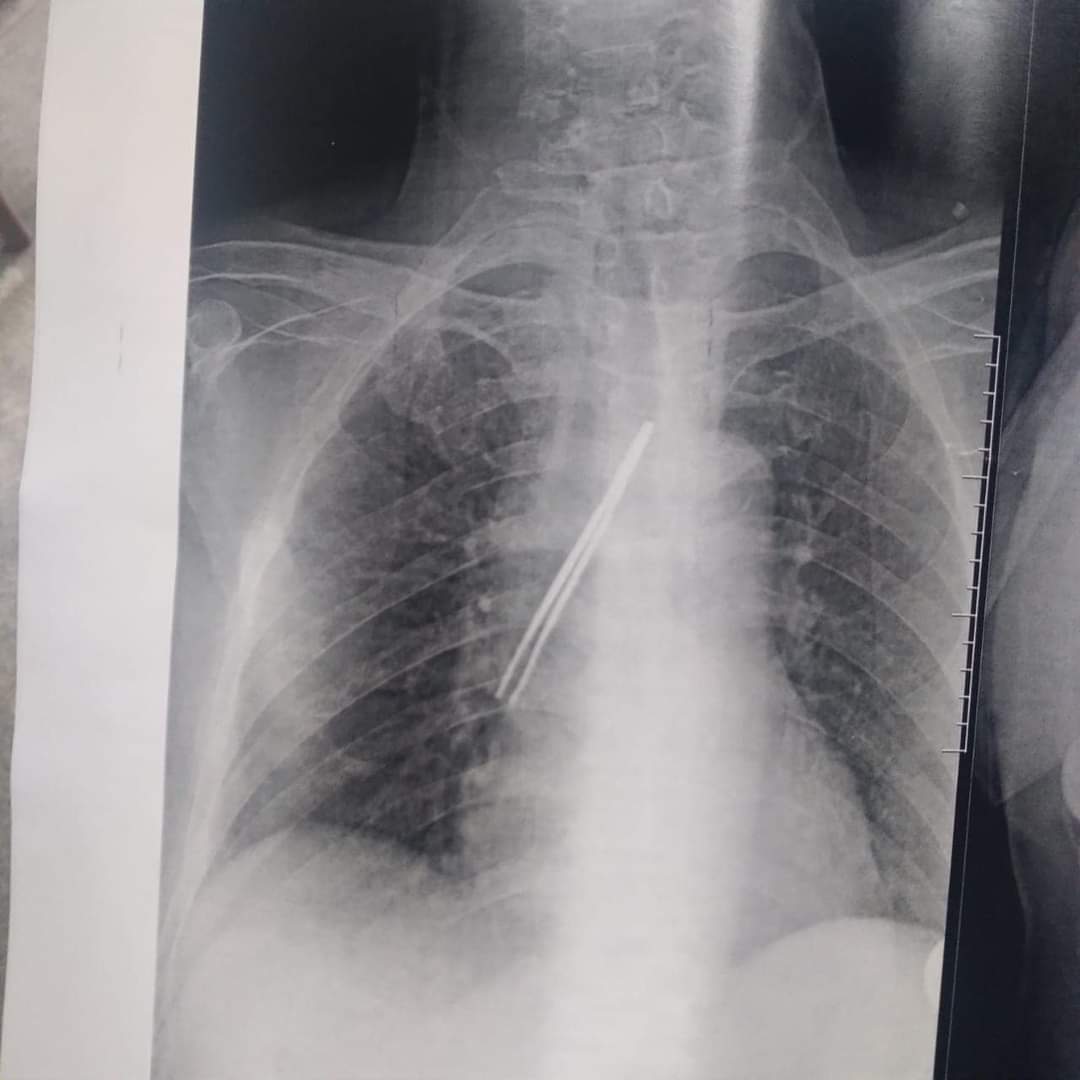

نجح فريق جراحي بقسم جراحة القلب والصدر بمستشفى بنها الجامعى بمحافظة القليوبية، في استخراج ملقاط شعر، من القصبة الهوائية لمريض يعاني من شق حنجري قديم، وأثناء قيامه بتنظيف فتحة الشق الحنجرى بطريقة غير طبية وغير صحيحة باستخدام ملقاط ملفوف بمناديل ورقية، سقط منه وابتلعه ودخل لفتحة القصبة الهوائية.

وأوضح مستشفى بنها الجامعي بمحافظة القليوبية، في بيان له، أنه تم استخراج ملقاط شعر من القصبة الهوائية لمريض يعاني من شق حنجري قديم، وبينما يقوم بتنظيف فتحة الشق الحنجري بطريقة غير طبية وغير صحيحة باستخدام ملقاط ملفوف بمناديل ورقية سقط داخل فتحة القصبة الهوائية.

وتابع المستشفى، أن المريض حضر للقسم في حالة اختناق، وتم دخوله للعمليات فورا، حيث نجح الدكتور باسم مفرح الأستاذ المساعد بالقسم، وبمعاونة الدكتور أحمد الخضري مدرس مساعد التخدير، من استخراج الملقاط، وخرج المريض من العمليات، ويخضع لاستكمال علاجه بالقسم لحين تماثله الكامل للشفاء.